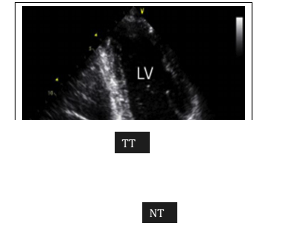

5.1.2. Cắt ngang van ĐMC và nhĩ trái

Từ trước ra sau, thấy các cấu trúc: Thành trước lồng ngực, thành trước thất phải, buồng tổng máu thất phải, thành trước ĐMC nối liền bằng VLT (sự liên tục van hai lá - ĐMC), buồng NT, thành sau NT.

Quan sát được 2 trong 3 lá van sigma của ĐMC: Lá vành phải và lá không vành. Vận động các van sigma động mạch chủ khi mở tạo thành “hình hộp”.

Các thông số cần đo trên mặt cắt này:

- Đường kính cuối tâm trương ĐMC.

- Biên độ mở van ĐMC.

- Đường kính cuối tâm thu của nhĩ trái.

Hình 2. Hình ảnh siêu âm tim TM: cắt ngang ĐMC và NT